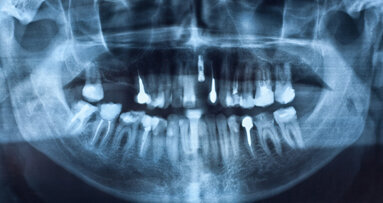

Die Auswirkungen der chronischen Entzündung des Zahnhalteapparates auf den restlichen Körper wurden schon in zahlreichen Studien belegt. So werden Diabetes, verschiedenen Krebsarten oder auch kardiovaskuläre Erkrankungen mit Parodontitis assoziiert. Eine aktuelle Untersuchung, die beim 47th Annual Meeting of the American Association for Dental Research vorgestellt wurde, zeigt nun, dass Parodontitis auch zum Erblinden führen kann.

Für ihre Studie untersuchten die Forscher den Zusammenhang von Porphyromonas gingivalis, dem Markerkeim für Parodontitis, und der altersbedingten Makuladegeneration, eine Hauptursache für schwere Sehbehinderungen ab 60 Jahren. Da bereits bekannt ist, dass sich Porphyromonas gingivalis im gesamten Körper z. B. über Makrophagen ausbreiten kann, wurde seine Wirkung auf retinale Pigmentepithelzellen genauer betrachtet. Im Test mit Mäusen konnten die Wissenschaftler zeigen, dass der Markerkeim der Parodontitis die retinalen Zellen angreift, damit nachhaltig schädigt und so zur altersbedingten Makulardegeneration beiträgt.